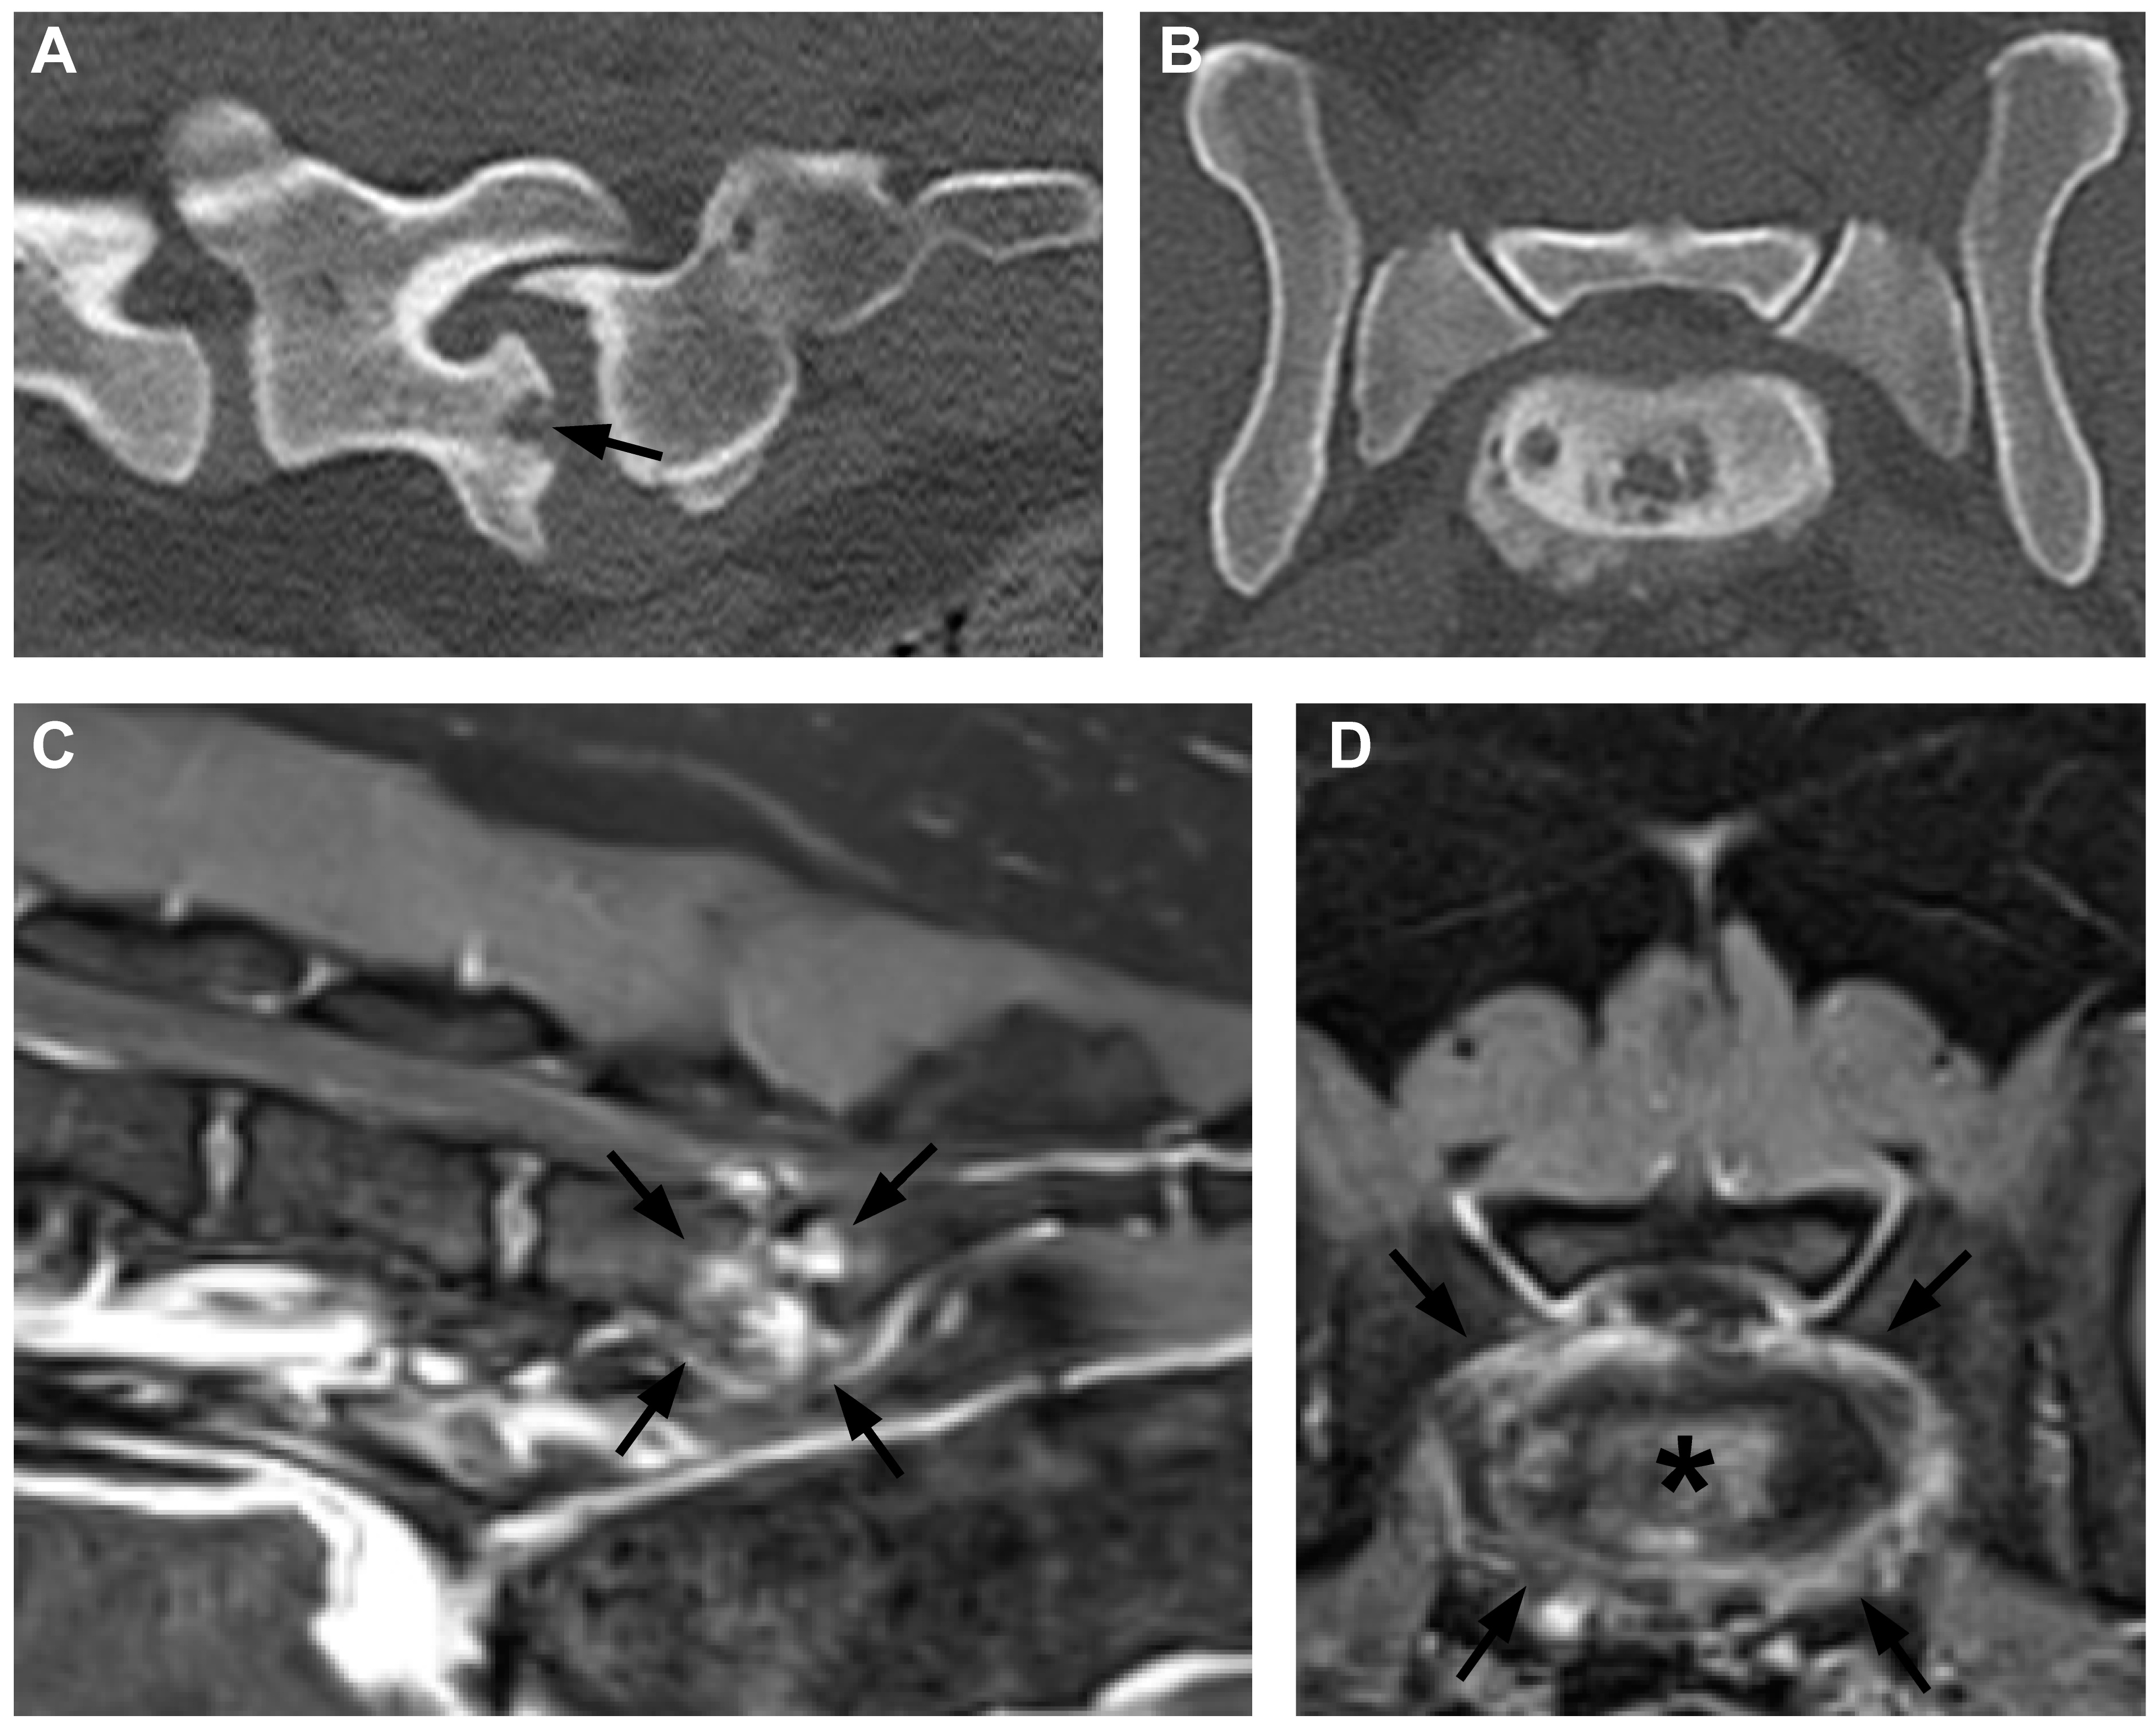

Dogs with a diagnosis of suspected fungal discospondylitis tended to show larger areas of bone loss on CT, that sometimes included ragged, rough-edged regions of bone loss with less obvious neighboring sclerosis but with more pronounced neighboring proliferative bone (Figure 2).

Figure 2. CT and MR images of discospondylitis in a dog in which fungal infection had been diagnosed by galactomannan antigen testing. (A) Mid-sagittal CT of the mid-lumbar region and (B) transverse CT through the cranial aspect of L4 indicated by line in (A). Note the multifocal lesions (arrows in A) and combined bone proliferation and lysis in (B). (C) Mid-sagittal and (D) transverse T1-weighted plus contrast MR images corresponding to the CT images. There is extensive contrast enhancement (*) in the vertebral bodies of L3 and L4 (in C) and within the vertebral endplate (in D).